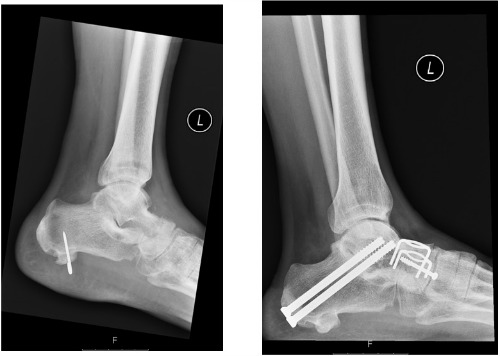

The surgical treatment of hindfoot arthritis involves permanently stiffening the joints with a fusion or 'arthrodesis'.

Fusion can be carried-out either as an arthroscopic (key-hole) or open procedure. The residual articular cartilage is removed from the joints before they are fixed together in a functional position with screws or plates allowing the bones to heal together. This means the painful joints no longer rub together and pain is alleviated.